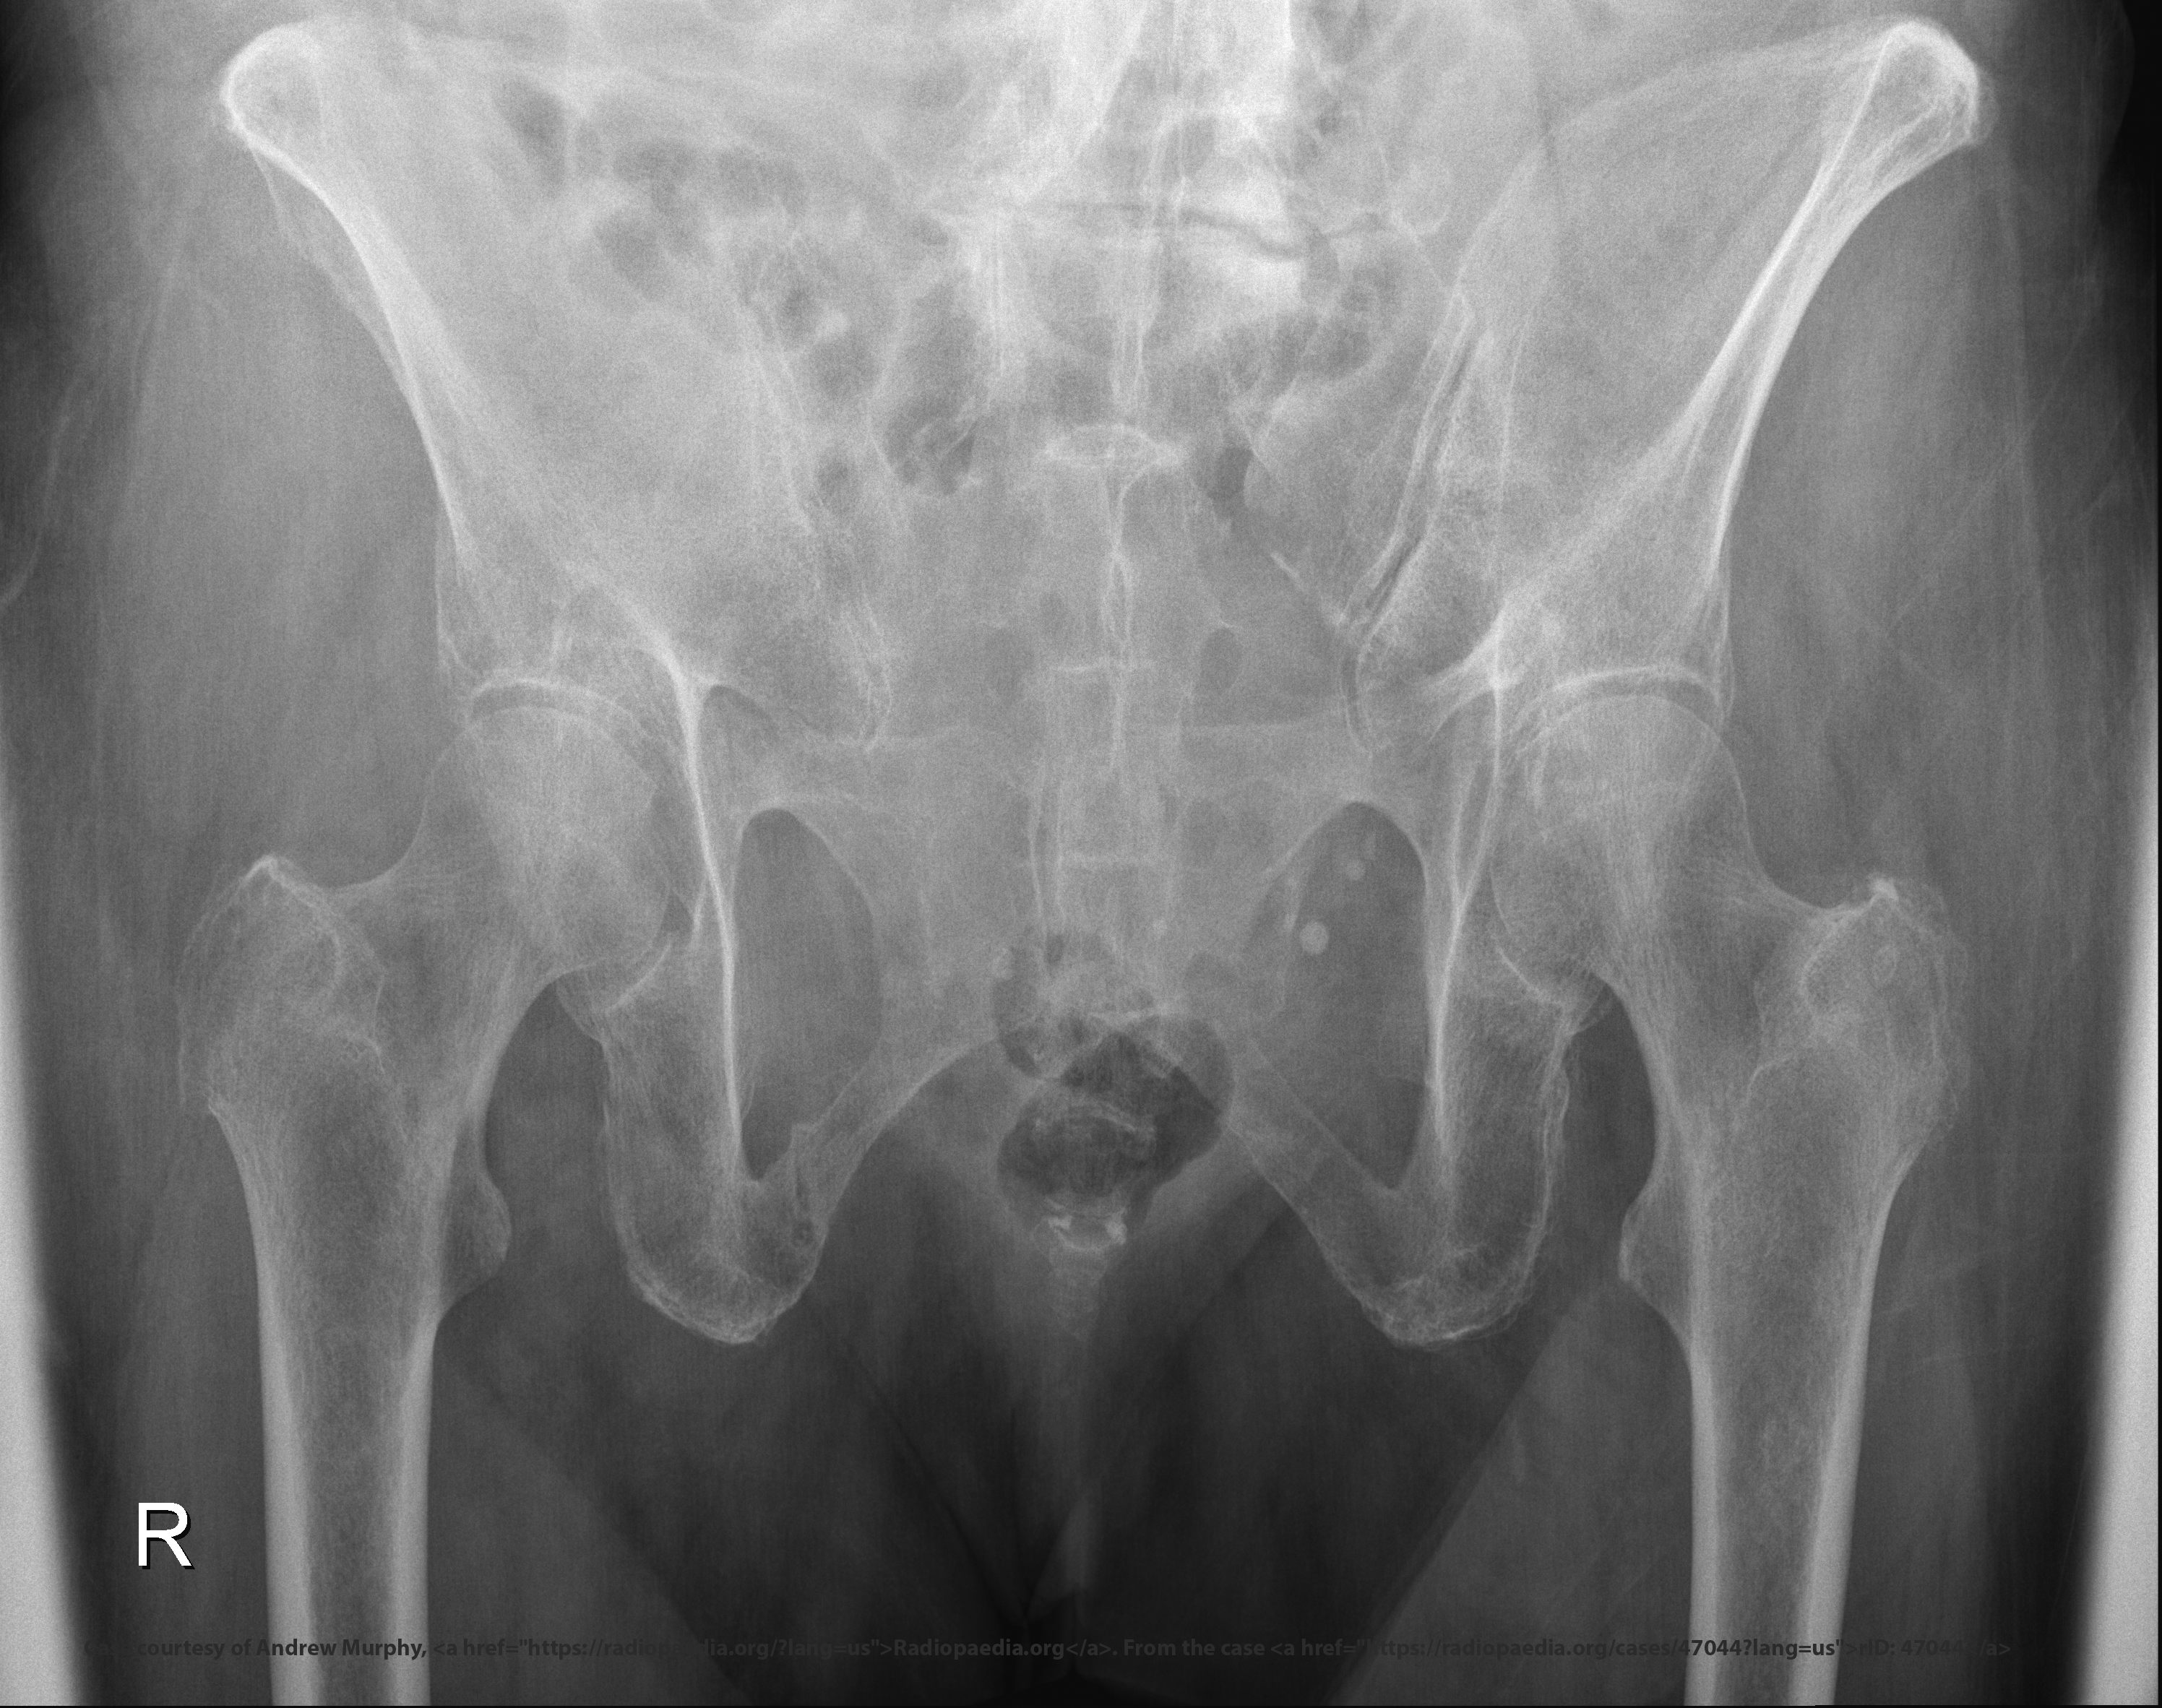

<p>What do inlet and outlet views evaluate?</p>

What do inlet and outlet views evaluate?

Pelvic fracture displacement and stability.

What displacement does inlet projection show?

Anterior/posterior displacement.

What is the CR angle for an inlet projection?

40° caudad.

What is the patient position for both inlet and outlet projections?

Supine, no rotation, legs extended.

<p>Supine, no rotation, legs extended.</p>

What anatomical structures does the inlet projection demonstrate?

Pelvic brim, anterior pelvis, acetabulum.

<p>Pelvic brim, anterior pelvis, acetabulum.</p>

Why are both inlet and outlet views often ordered together?

Each reveals different fracture displacement.

Which projection helps assess anterior-posterior instability?

Inlet.

<p>Inlet.</p>